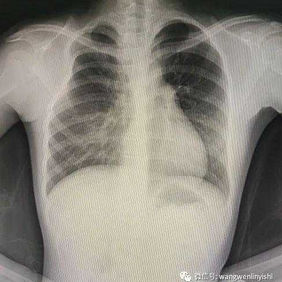

The patient is an 11-year-old girl who has had chest wall deformity since childhood. Despite being diagnosed with Poland syndrome at the age of 6, she did not undergo any treatment. From the age of 10, her left mammary glands began to develop while the right one did not, resulting in progressively severe asymmetry of her chest wall.

The chest wall exhibits asymmetry with the left mammary glands developing normally, whereas the right side of the chest wall has a depression. This asymmetry is further characterized by a defect in the right pectoralis major, underdevelopment of the right mammary glands, and detachment of the third costal cartilage from the ribs on the right side.